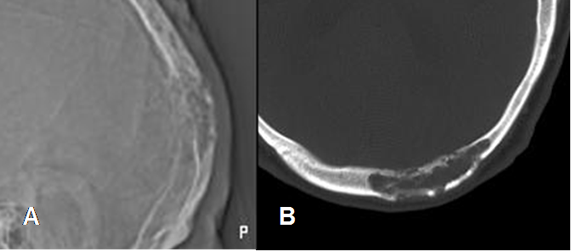

Fig 155. Hemangioma óseo.

A: Rx lateral y B: TAC axial. Lesión permeativa que expande y compromete ambas tablas óseas.

Fig 156. Hemangioma óseo.

A: Rx lateral y B: TAC axial. Lesión radiolúcida y de contornos definidos y no escleróticos.